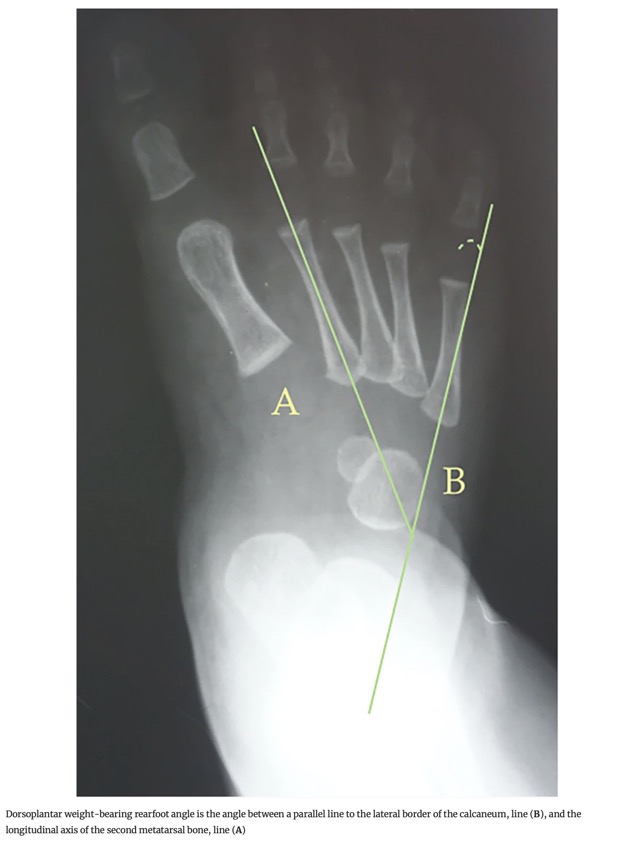

- 2. Angle dorsoplantaire du talon en charge